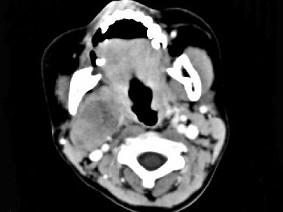

问题 女,4岁,右侧颈部可扪及一包块约两个月,无热无痛,CT如图所示,最可能的诊断为 ( )

选项 A、咽旁神经纤维瘤 B、咽旁小唾液腺混合瘤 C、咽旁副神经节瘤 D、咽旁脓肿 E、咽旁血管外皮瘤

答案 A